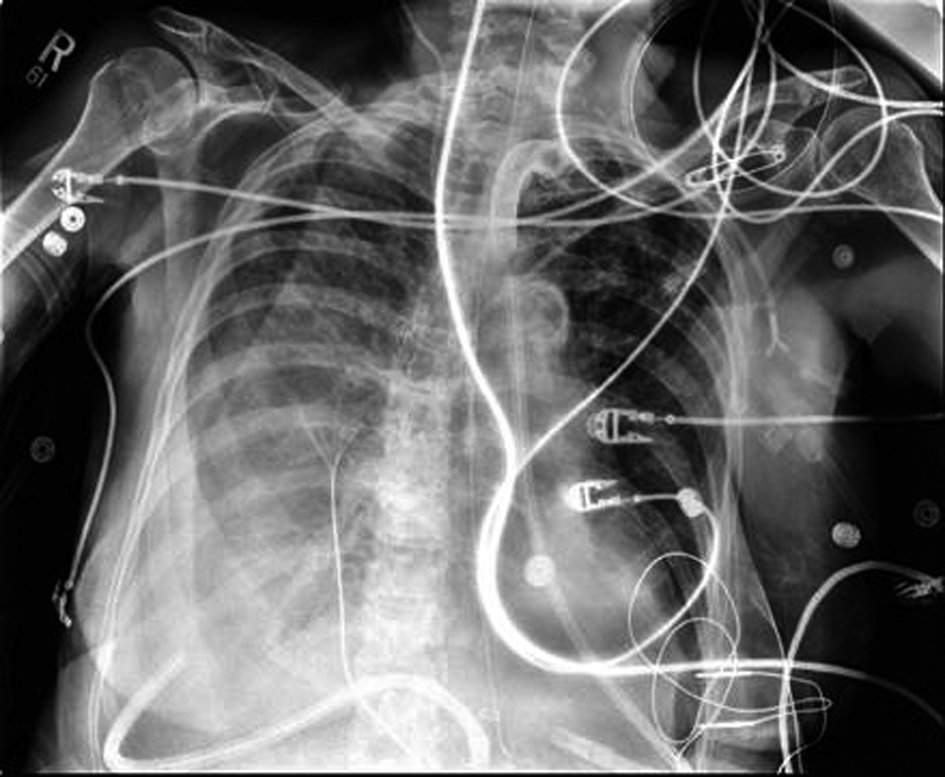

The patient underwent a THE as well as placement of a feeding jejunostomy tube. As per our standard practice, Jackson-Pratt (JP) drains were placed in the pleural spaces bilaterally via the mediastinal hiatus to prevent the collection of any possible post-operative effusions (Fig. 1). The patient tolerated the procedure well but post-operatively the patient deteriorated into respiratory failure requiring re-intubation and transient vasopressor support. By the third post-operative day, a second attempt of extubation had failed and the decision for early tracheostomy placement was made to assist with long-term ventilatory support. Slightly more than one week post-operative, the right thoracic JP drain was noted to be draining about 5 L of serous fluid daily. There was evidence of increasing right sided pleural effusions on chest X-ray (Fig. 2). Drainage continued at an average of more than 4 liters per day, with a peak output of nearly 6 liters at one measurement. As enteral feeds were initiated via the jejunostomy, it was noted the pleural effluent changed from serous to white, opaque, and fatty. The suspicion of chyle leak was confirmed with elevated triglyceride level from the draining fluid. As enteral feeds were stopped, JP output moderately decreased and again became transparent. Octreotide and parenteral nutrition were initiated for attempted conservative management of the chylothorax. This management failed, however, as the daily chylous thoracic output persisted at an average of more than 3 L per day. A lymphoscintigram failed to locate the specific source of the lymphatic leak therefore targeted embolization/ligation of the thoracic duct via interventional radiology was precluded.

![]() Click for large image | Figure 2. Post-operative day 9; development of right chylothorax. |